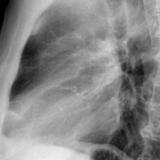

Calc Ao valve & LtA